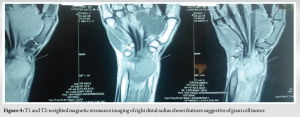

Magnetic resonance imaging of right wrist joint (Fig. 4) shows diffuse aggressive expansile heterogenous lytic lesion with articular extension in the distal end of radius of length 3.8 cm involving the epiphyseal and meta-diaphyseal region with narrow zone of transition with cortical breach in the anterior and posterior aspect of lesion with extraosseous anterior and posterior projections. Initially, core needle biopsy of right distal radius lesion at its proximal margin from the dorsal side was done and diagnosis of GCT of right distal radius was confirmed. After that the patient was planned for definitive management.